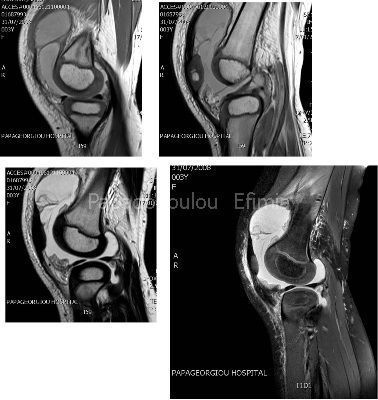

ΜΑΓΝΗΤΙΚΗ ΤΟΜΟΓΡΑΦΙΑ ΑΡ ΓΟΝΑΤΟΣ

Ζητάς MRI ΑΡ γόνατος που γίνεται το επόμενο πρωί και δείχνει: παρουσία σημαντικής ποσότητας στο μεσάρθριο χώρο, στον  υπερεπιγονατιδικό θύλακο και στους πλάγιους θυλάκους (στις άνω εικόνες απεικονίζεται η περίσσεια του αρθρικού υγρού με ανοιχτό γκρί χρώμα).  Στις κάτω εικόνες φαίνεται  η έντονη πάχυνση του συνοβίου που εμπλουτίζεται έντονα με σκιαστικό (συνοβίτιδα). Η πάχυνση του συνοβίου  απεικονίζεται με κυματοειδή εμφάνιση .